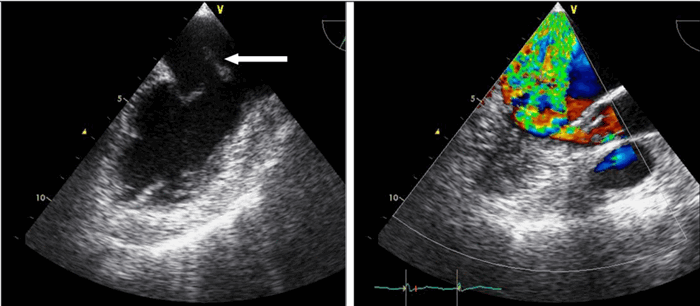

Техническая справка: Эхокардиография с допплерометрией и ЦДК

Эхокардиография с допплерометрией и цветным допплеровским картированием (ЦДК) – это сочетание обычного двумерного ультразвукового сканирования сердца для анализа его анатомии с допплерометрией. Эффектом Допплера называется физическое явление изменения частоты ультразвука при отражении его от движущихся объектов. Допплерометрия позволяет оценить ток крови, его направление, скорость и характер, а в сердце выявить недостаточность и стеноз клапанов, отрывы хорды и т.д. Сочетание обычного двумерного серошкального УЗИ с допплерометрией плюс добавление цветовой кодировки потоков крови (от УЗ-датчика и к нему) – это цветное допплеровское картирование. С его помощью наши специалисты сразу видят патологические забросы крови (из полости левого желудочка во время систолы в левое предсердие при недостаточности митрального клапана).

Для облегчения выявления турбулентного движения (завихрений) существует порог скорости, выше которого происходит изменение цвета (во многих аппаратах это зелены). «Мозаичный» узор на участке турбулентного потока позволяет легко установить регургитацию (смену направления движения), что помогает определить степень недостаточности клапанов.

Так, например, эхокардиография с допплерометрией и цветным допплеровским картированием (ЦДК), которая является сочетанием 2D и М-режимов с допплерометрией, очень полезна при оценке митрального стеноза. Первые два способа визуализации позволяют заподозрить кальцификацию клапана (аномальное движение его створок).

Допплерометрия демонстрирует при этой патологии повышенную скорость кровотока (признак сужения) и может быть использована для оценки «эффективной площади отверстия» (степени выраженности стеноза).